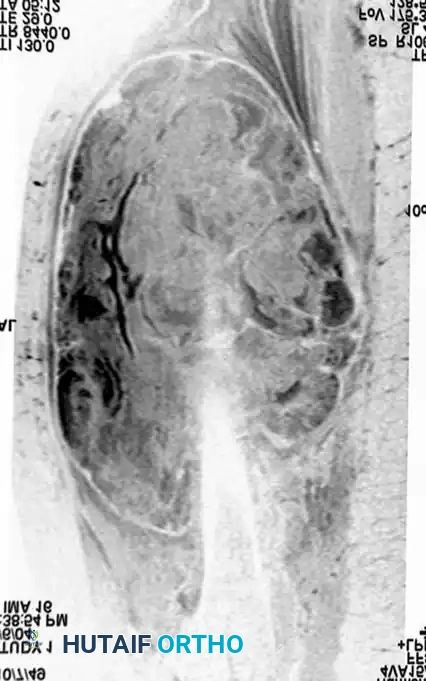

Imaging:

Conventional radiographs may demonstrate a non-specific soft-tissue density but are usually normal. MRI reveals a well-circumscribed mass that is typically isointense to muscle on T1-weighted images and hyperintense on T2-weighted images. Central necrosis is a hallmark of larger, high-grade tumors.

Axial MRI showing a large soft-tissue mass in the thigh with mixed signal intensity, characteristic of UPS/MFH.

Coronal MRI demonstrating the proximal-distal extent of the tumor within the muscular compartment.